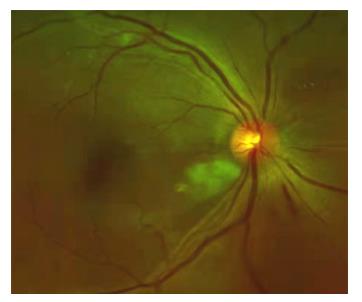

患者女,2 3岁,既往高血压病病史,因“左眼视物模糊1 3天”于2011年4月1 5日就诊于济宁医学院附属医院眼科,眼科查体:右眼视力为0.6,左眼视力为0.08,双眼眼前节情况正常,右眼眼底动脉反光增强,静脉略迂曲(图1),左眼眼底颞上方视网膜大片火焰状出血、棉绒斑、静脉迂曲、黄斑水肿(图2 )。眼底荧光血管造影示:左眼颞上方网膜大片荧光遮蔽,微血管瘤,未见明显无灌注区(图3 ),诊断“左眼视网膜分支静脉阻塞,双眼高血压视网膜病变”,给予随访观察,控制血压。发病36 d时,眼底检查见:左眼视盘新生血管(图4);眼底血管造影检查见:左眼视盘荧光渗漏,颞上视网膜大片无灌注区(图5),给予眼底病变区视网膜激光光凝治疗。发病75 d时,眼底检查见:左眼视盘新生血管增殖膜,颞上方视网膜血管闭塞,散在激光斑(图6,7 ),补充病变区激光治疗。发病103 d时,眼底血管造影检查见:左眼视盘荧光渗漏,颞上方视网膜异常血管网(图8,9 ),补充病变区激光治疗。发病138 d时,左眼视力为0.02,视盘形成新生血管膜,表面血管旺盛(图1 0,11),再次补充病变区激光治疗。1 0年后因“右眼视力下降3天”就诊,查体:右眼视力为0.4,左眼视力为0.4;眼底检查见:左眼视盘新生血管膜机化萎缩,表面无血管(图12),右眼后极部颞下、颞上视网膜棉绒斑,鼻下和鼻侧视网膜浅层出血,鼻上视网膜少许硬性渗出(图13)。

图1 右眼眼底彩照:动脉反光增强,静脉略迂曲(发病13 d)

Figure 1 Color fundus of the right eye showed enhanced arterial reflection and slightly tortuous veins (oneset of 13 d)